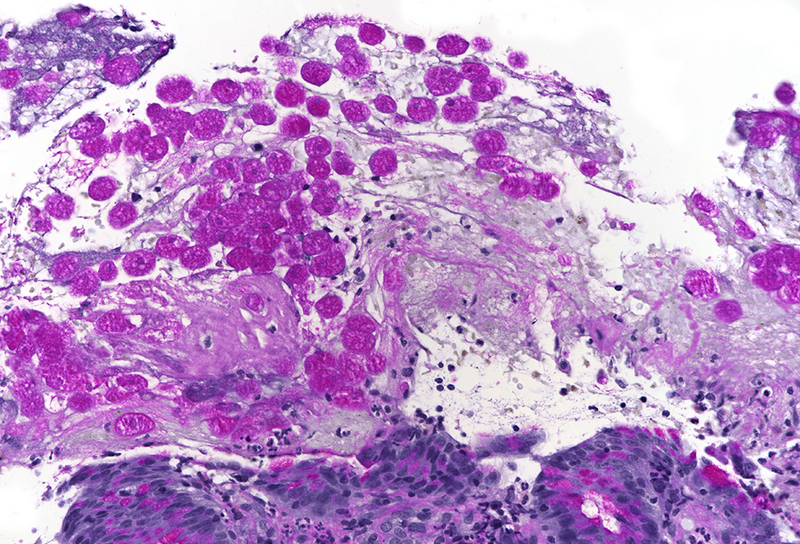

Histology revealed colonic mucosa with preserved architecture. Multiple erosions, crypts with degenerative features and increase of the inflammatory cell infiltrate in the lamina propria, especially granulocytes, were observed (PANEL A-B). On the luminal surface, accompanied by fibrin and debris, multiple organisms with roundish shape, foamy cytoplasm and round, pale and eccentric nuclei were found; some of those have erythrocytes engulfed in their cytoplasm (PANEL C-D); periodic acid-Shiff (PAS) stain highlights these organisms (PANEL E-F), which qualify for diagnosis of amoebiasis.

Histologically, initial lesions show a mild neutrophilic infiltrate, with numerous organisms present at the luminal surface associated with detritus. In advanced disease, ulcers are often deep, extending into the submucosa, sometimes with invasive amoebae within the bowel wall. Entamoeba histolytica has a roundish shape, with foamy cytoplasm and round, pale and eccentric nuclei with an open nuclear chromatin pattern. Within the inflammatory exudate, they may be difficult to distinguish from macrophages; in these cases, histochemical and immunohistochemical stains may be performed: amoebae are trichrome- and PAS-positive and macrophages stain with CD68. It is noteworthy the presence of ingested erythrocytes as pathognomonic feature of this parasite.